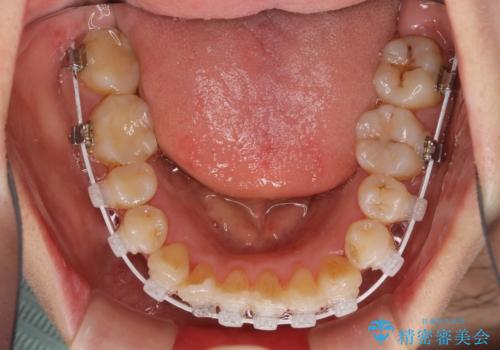

狭い上顎骨を拡大 著しい叢生を抜歯矯正で改善

骨格的に上顎は狭く、下顎は右側にシフトしていたため、右側臼歯はクロスバイトとなっていました。

治療途中、長期間海外旅行をされたり、帰国後には遠方へ転居されたりと、治療期間が伸びましたが、2年強で治療を終えることができました。